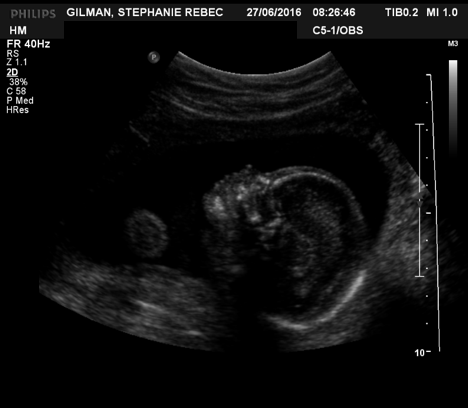

On November 7th, 2016, I Â went for an ultrasound to check on my baby. I’d been having issues with my placenta and they were monitoring it to make sure the baby was still getting everything he needed. After the ultrasound, I spoke with the radiologist to discuss the latest results.